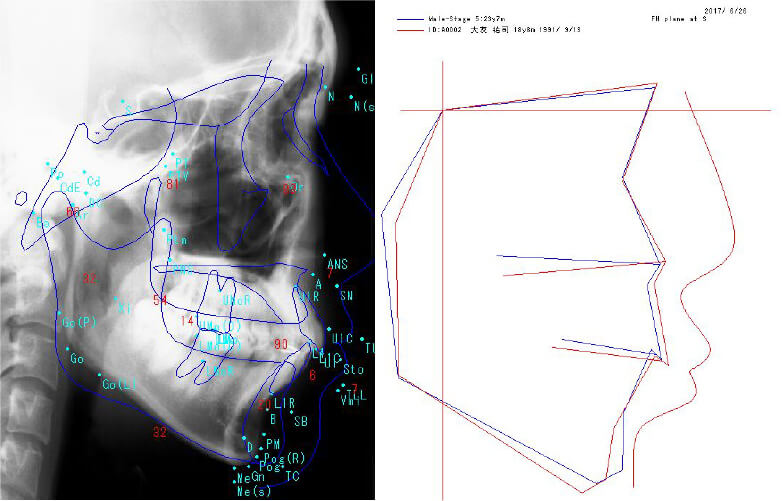

セファロは、矯正治療に必要とする透過性の高い画像を撮影することができます。

多彩な分析機能を備えており、治療前、治療中、治療後の歯の動きが詳細にわかりますので、

患者様お一人おひとりに最適な治療計画をご提案することができます。

トレースの作成や線分析・角度分析などの各種分析が可能です。